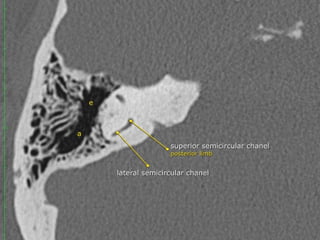

The semicircular canals

 are components of the bony labyrinth within the

petrous temporal bone (PTB) along with the cochlea and vestibule.

They contain the semicircular ducts, part of the

membranous labyrinth which are responsible for kinetic balance.

 There are three semicircular canals on each side, each forming two

thirds of a full circle which are orientated perpendicular (at right

angles) to each other. They all open into the vestibule. They have

differing and variable lengths but uniform diameters of approximately

1 mm.

 Each semicircular canal has a dilatation termed ampulla at one end,

the posterior and superior semicircular canals share a common crus

formed by the fusion of the posterior crus of the superior semicircular

canal and the anterior crus of the posterior semicircular canal, which

then opens into the superomedial part of the vestibule, the lateral

semicircular canal, on the other hand, has two separate openings

into the vestibule

 Superior (anterior) semicircular canal (SSCC)

orientated in the vertical plane perpendicular (transverse) to the long axis of the

PTB. it lies under the arcuate eminence on the anterior surface of the PTB. Hair

cells of the superior semicircular duct supplied by the superior division of the

vestibulocochlear nerve (CN VIII). Seen perpendicular to long axis of

temporal bone

 Posterior semicircular canal (PSCC)

orientated in the vertical plane parallel to the long axis of the PTB

hair cells of the posterior semicircular duct supplied by the inferior division of CN

VIII

Lateral (horizontal) semicircular canal (LSCC)

orientated 30 degrees to the horizontal. shortest of the semicircular canals

hair cells of the lateral semicircular duct supplied by the superior division of CN

VIII.

** Signet ring appearance